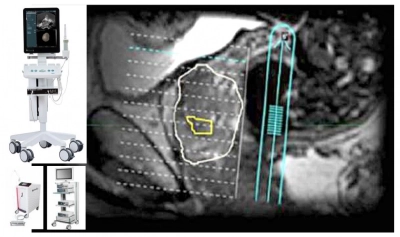

• Ecograful BK3000 – permite, pentru afecțiunile prostatei, fuziunea în timp real a imaginii ecografice cu imaginea RMN multiparametric și astfel pacienții beneficiază de biopsii rapide și țintite. Aparatul disponibil la Sanador este unic în România.

• Echipamente RMN performante: Siemens Magnetom Skyra 3 T (unic în țară), Philips Achieva dSTREAM 1,5 T și Siemens Magnetom Avanto 1,5 T. Imagistica prin rezonanță magnetică (IRM sau RMN) este una dintre cele mai avansate tehnici de imagistică medicală, care permite medicului să diagnosticheze rapid și precis o gamă extinsă de afecțiuni. IRM permite medicului vizualizarea unor detalii foarte specifice ale organelor și țesuturilor, adăugând informații care nu ar putea fi obținute prin tomografie computerizată, radiologie standard sau ecografie.